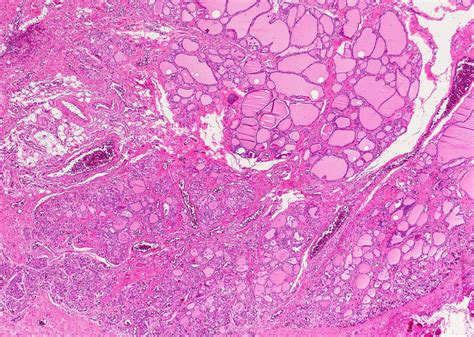

• Surgical excision: The most definitive treatment for a Cyst Thyroglossal Duct is surgical excision, also known as the Sistrunk procedure. This involves removing the cyst along with a portion of the hyoid bone and the central portion of the tongue base to prevent recurrence.

The Sistrunk procedure is the gold standard for the surgical excision of a Cyst Thyroglossal Duct. This procedure involves the following steps:

• A portion of the hyoid bone and the central portion of the tongue base are removed to ensure complete excision of the cyst and prevent recurrence.